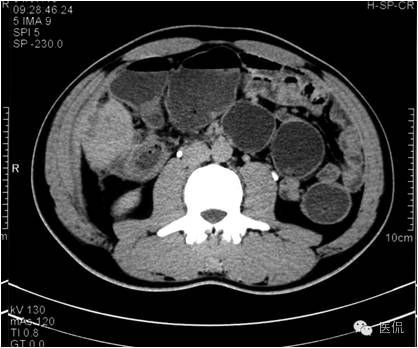

门脉期上述部位持续强化,程度加重,且环壁影增厚,核心样结节、分隔明显。